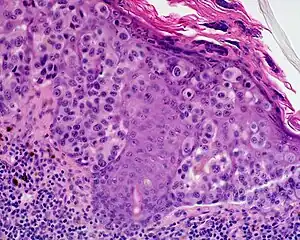

Lentigo maligna melanoma is a melanoma that has evolved from a lentigo maligna,[1]: 695 as seen as a lentigo maligna with melanoma cells invading below the boundaries of the epidermis.[2] They are usually found on chronically sun damaged skin such as the face and the forearms of the elderly.

An invasive tumor arising from a classical lentigo maligna. Usually a darkly pigmented raised papule or nodule, arising from a patch of irregularly pigmented flat brown to dark brown lesion of sun exposed skin of the face or arms in an elderly patient.